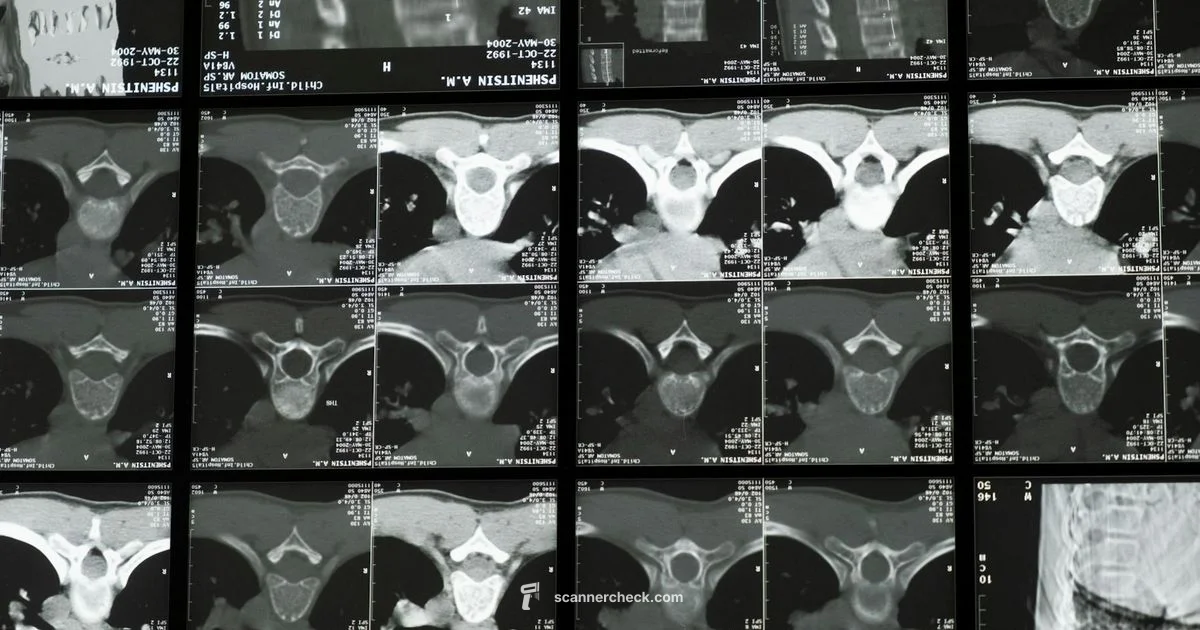

ct scanner metal is a phenomenon where metal objects within or near a CT scanner cause image artifacts such as streaks and shading, due to beam hardening and photon starvation. These artifacts can affect diagnostic confidence and require artifact reduction strategies.

According to Scanner Check, ct scanner metal is a phenomenon where metal objects near or within a CT scanner cause image artifacts. These artifacts manifest as bright and dark streaks and regions of altered density that can obscure anatomy and complicate interpretation. The underlying mechanism combines beam hardening, where dense metals preferentially absorb low energy photons, with photon starvation in dense materials and scatter from surrounding tissue. The result is a nonuniform projection data set that translates into streaks across several slices. Recognizing these patterns helps radiographers and clinicians distinguish true pathology from artifact and guides the choice of artifact reduction techniques, scan protocols, and postprocessing options. This understanding lays the groundwork for selecting the most appropriate imaging approaches for patients with dental work, implants, or external hardware.

Metal artifacts arise primarily from three physical processes: beam hardening, photon starvation, and scatter. High atomic number metals absorb a broad spectrum of X ray energies unevenly, shifting the spectrum toward harder energies and creating dark or bright streaks adjacent to the metal. Dense implants can consume many photons, leading to gaps in data, while scattered photons from surrounding tissues contribute to blurred edges and unnatural shading. The geometry and composition of the hardware, along with the scanning angle, determine how pronounced the artifacts appear. In practice, recognizing the signature patterns—long streaks along metal contours, wedge-shaped shading, and localized distortions—helps differentiate artifacts from real pathology and informs mitigation strategies.

In everyday CT practice, several metal sources frequently contribute to artifacts. Dental fillings, crowns, and implants are among the most common culprits due to their high density and irregular shapes. Orthopedic hardware such as plates, screws, rods, and joint prostheses also produce artifacts, especially when located near the region of interest like the spine or pelvis. Surgical clips and vascular stents can contribute as well, depending on their material and nearby anatomy. Even external devices like lead aprons or supportive hardware can interact with the scan under certain conditions. Being aware of these sources helps imaging teams preemptively adjust protocols and apply artifact-reduction techniques.